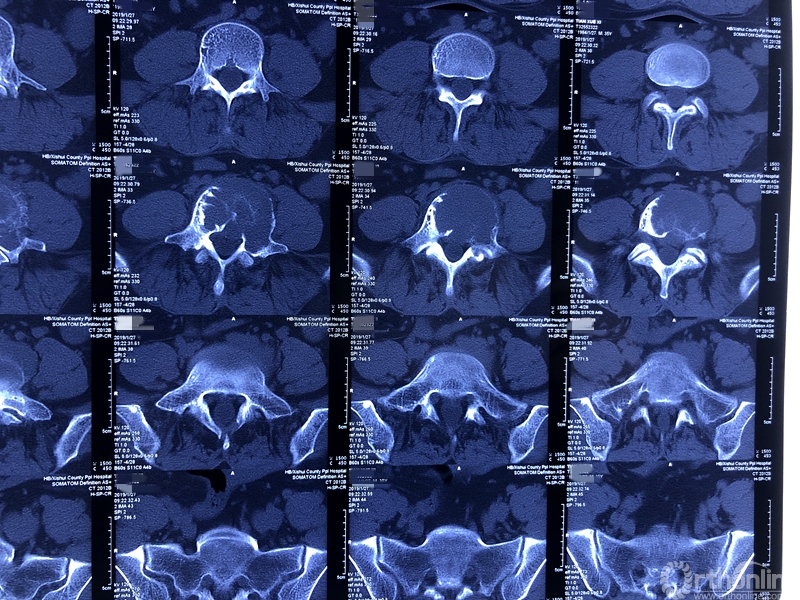

就诊前CT

通过对患者详细的身体检查、穿刺活检和综合评估后,确诊患者是腰椎骨巨细胞瘤,第五腰椎破坏70%以上,邻近软组织也有破坏。这种肿瘤属于交界性的有恶性倾向的良性肿瘤,若不彻底切除,患者疼痛会逐渐加剧,甚至因骨质坍塌而瘫痪,若肿瘤细胞转移更会危及生命。若是能在早期尽快彻底、完全地切除肿瘤及被侵蚀椎体,病人才很可能完全战胜肿瘤。